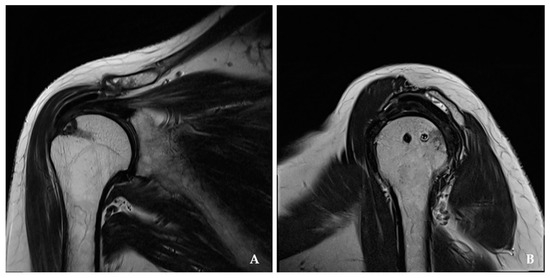

2.2. Clinical and Radiologic Assessment

3.3. Radiologic Assessment